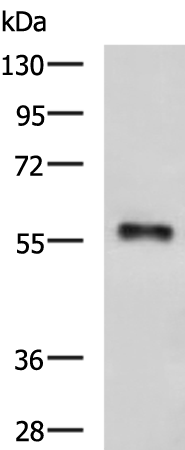

分类: 科研抗体货号: P10202别名: GST2; ERF3B应用: WB,IHC反应种属: Human, Mouse